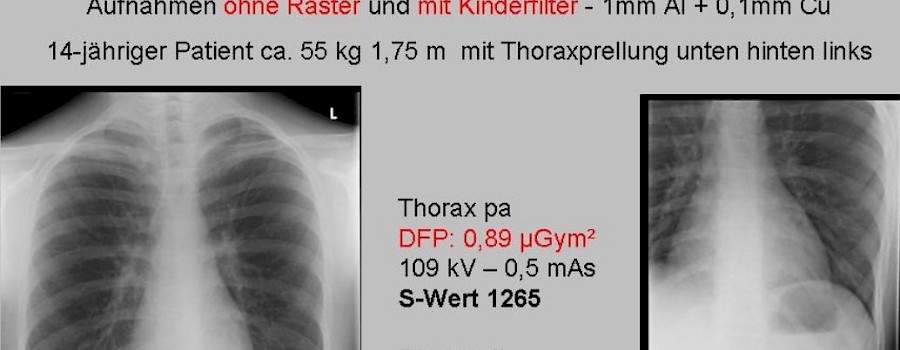

Ein Beispiel dafür wie man mit geringster Dosis optimale Ergebnisse erreicht und dennoch die Fragestellung des Arztes, der die rechtfertigende Indikation stellt, zu dessen voller Zufriedenheit beantworten kann.